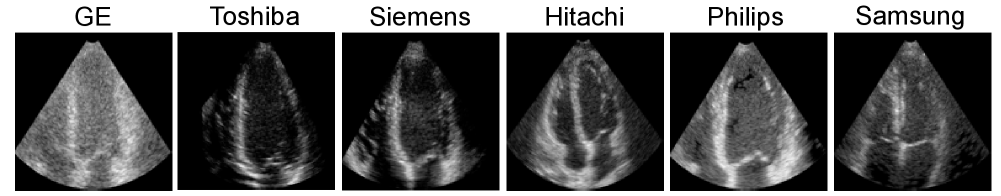

To train a deep network for clutter removal from input TTE sequences, corresponding artifact-free output sequences are required. The use of artifact-free outputs is important to ensure that the network learns to accurately differentiate between clutter and signals of interest. A dataset of ultra-realistic synthetic 2D TTE sequences [alessandrini2017realistic] was used for this purpose in our experiments. The dataset comprised 90 vendor-specific TTE sequences from different ultrasound systems. For each vendor, five distinct myocardial motion patterns (one normal and four ischemic) were simulated in apical two-, three-, and four-chamber views. These synthetic motion patterns were generated using a complex electromechanical heart model, while vendor-specific speckle texture patterns were derived from real clinical TTE recordings.

The synthetic 2D frames from six vendors were resized to pixels, and 50 frames were combined to form 2D TTE sequences with dimensions of for training the deep filtering network. Figure 1 shows examples of apical four-chamber view images of the normal subject from these six vendors. As illustrated, the left and right heart chambers exhibit distinct appearances across the vendors. This inter-vendor variability makes the synthetic dataset well-suited for training a deep clutter filtering network, allowing for effective artifact filtering from diverse TTE images.